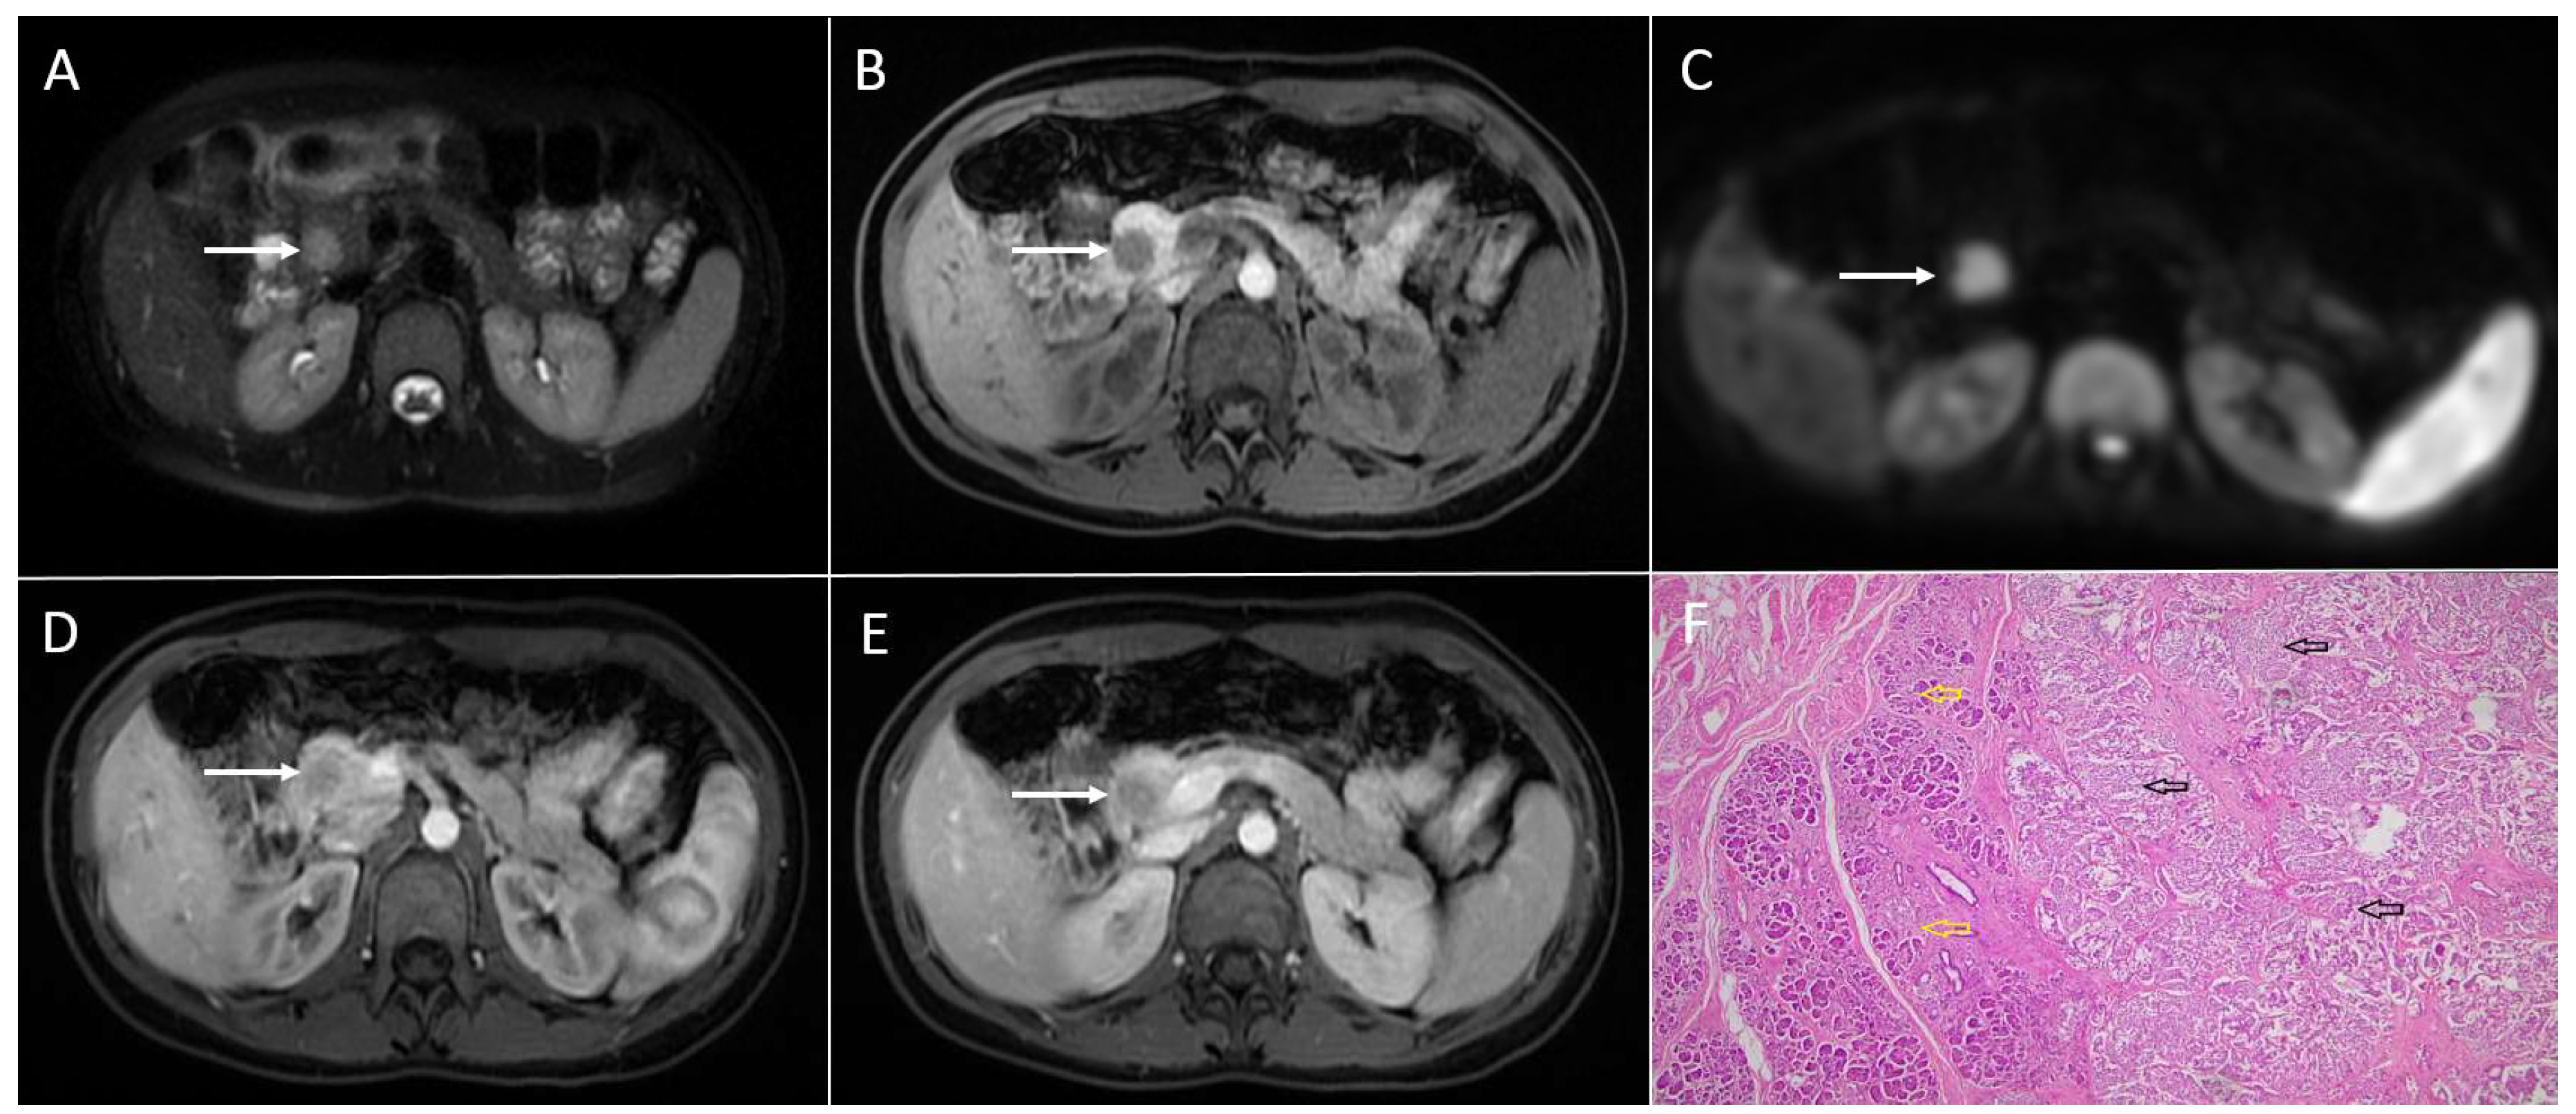

3.2. Pancreatic Adenocarcinoma

3.3. Intrapancreatic Accessory Spleen